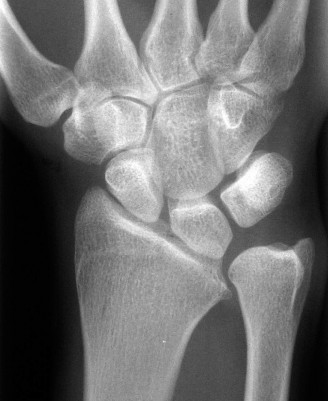

-

ray (Fig. 3–11) taken at the time of the visit is as shown. The radiologist reports this as SLAC wrist. What does SLAC stand for?

Figure 3–11(©) Sunil Thirkannad and Christine M. Kleinert.

The correct answer is (C).

The correct answer is (B). The patient has a severe SLAC wrist with involvement of the midcarpal joint. Loss of cartilage over the proximal pole of the capitate precludes a proximal row carpectomy. By the same token, interposition arthroplasty at the radio carpal joint alone fails to address the midcarpal problem. The use of a silastic prosthesis for the scaphoid has been abandoned due to very high rates of failure. Objectives: Did you learn...? Properly perform the Watson’s test? Identify a SLAC wrist and treat it? CASE 13 ### A patient presents with a history of chronic wrist pain of 6 years duration. He stated that he sustained a fall 9 years ago. Immediately after injury, he did not seek any medical attention, thinking that he had merely sprained his wrist. An xray taken at this visit is shown (Fig. 3–12). What does he have?